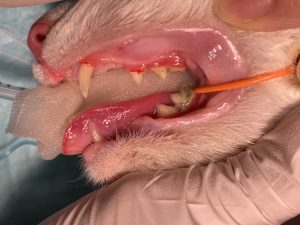

次の写真を見てみましょう。

この症例は歯磨き教室先生から歯が少ないことの指摘を受けて受診されました。

この子は3歳になる成犬ですが、上顎の第一から第三前臼歯と下顎の第一、第二、第四前臼歯が萌出していません。